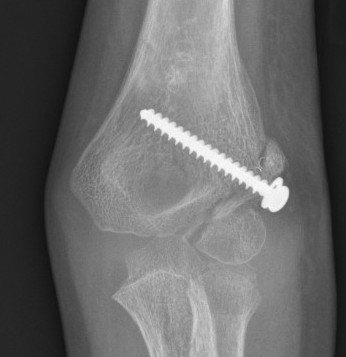

In situ screw fixation delayed nonunion

Results

Park et al J Paediatr Orthop 2015

- in situ fixation of 16 cases of nonunion with screw

- average 5 months post surgery with average 6 mm displacement

- all united

- 3/16 residual deformity